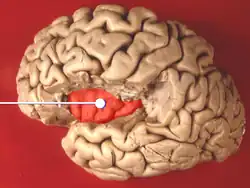

Model images

-

Inferior view of cerebrum.

Inferior view of cerebrum. -

Lateral view of left hemisphere.

Lateral view of left hemisphere. -

Both hemispheres. Left and right lobes are color-matched.

Both hemispheres. Left and right lobes are color-matched. -

-

-

Brain lobes and olfactory bulb.

Brain lobes and olfactory bulb.